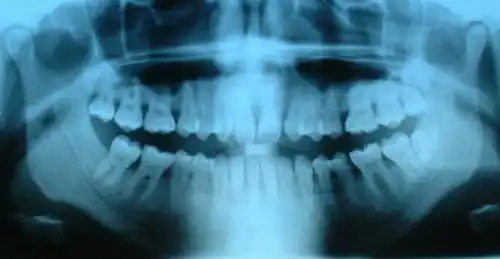

- On voit à la fois des dents temporaires et des dents définitives.

- Radiographie de dents saines (prémolaires, molaires, dent de sagesse incluse) et cariées (2e prémolaire supérieure et 1re molaire supérieure).